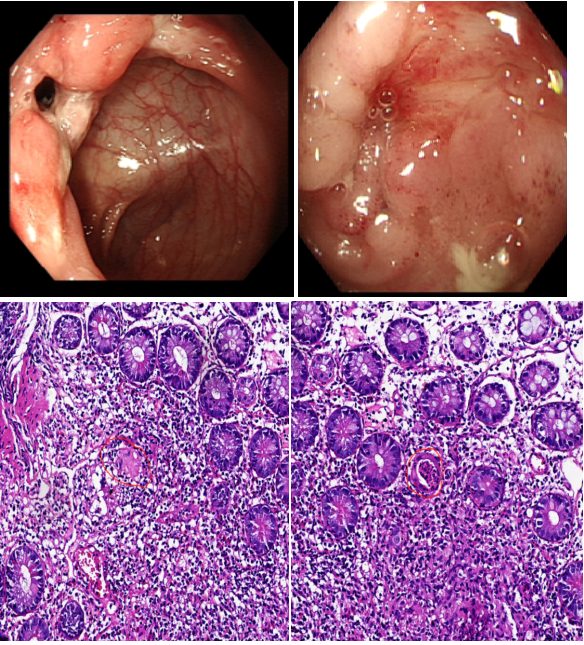

消化內(nèi)科二區(qū)通訊員譚思、李霞報道:近日,一位骨瘦如柴的24歲小伙慕名來到衡陽市中心醫(yī)院消化內(nèi)科二區(qū)就診。該患者因腹瀉1年有余,且伴有排便后肛周疼痛不適,輾轉(zhuǎn)多家醫(yī)院治療未果,整個人變得郁郁寡歡。接診時,患者體重僅有42KG,BMI只有14,肛周有一個1厘米左右的膿包,伴有觸痛。何小梅醫(yī)生立即給予安排小腸CTE及腸鏡等檢查,發(fā)現(xiàn)腸道有節(jié)段性的潰瘍病變。病區(qū)主任舒寶蓮綜合臨床表現(xiàn)、生化指標(biāo)、小腸CTE、腸鏡及病理結(jié)果,診斷患者為“克羅恩病肛周病變”。在對患者疾病的活動程度進(jìn)行評估后,基于患者年齡以及伴有肛周膿腫2項(xiàng)高危因素綜合考慮,給與患者使用生物制劑“英夫利西單抗”對癥治療。目前,患者腹瀉及肛周疼痛有明顯的好轉(zhuǎn),患者及其母親對診療效果非常滿意。出院時,患者充滿感謝地對醫(yī)務(wù)人員說:“醫(yī)生很快就找到了病因,又通過個體化的營養(yǎng)治療增加了我的體重,醫(yī)務(wù)人員還耐心地對我進(jìn)行健康宣教與心理疏導(dǎo),謝謝你們解決了困擾我生活的大問題。”

克羅恩?。?/span>CD):是一種病因尚不明確的胃腸道慢性炎性肉芽腫性疾病。病變多見于末端回腸和臨近結(jié)腸,但從口腔至肛門各段消化道均可受累,呈節(jié)段性或跳躍式分布。臨床上以腹痛、腹瀉、體重下降腹塊、瘺管形成、肛周病變及腸梗阻為特點(diǎn),可伴有發(fā)熱的全身表現(xiàn)以及關(guān)節(jié)、皮膚、眼、口腔粘膜等腸外損害。發(fā)病年齡多在15-30歲,但首次發(fā)作可出現(xiàn)在任何年齡組。本病有終生復(fù)發(fā)傾向,重癥或者遷延不愈。預(yù)后不良??捎心c梗阻、腹腔膿腫、消化道出血及結(jié)癌變等并發(fā)癥發(fā)生。

克羅恩病的診斷需結(jié)合臨床表現(xiàn)、實(shí)驗(yàn)室指標(biāo)、影像學(xué)(小腸CTE)、腸鏡及病理。